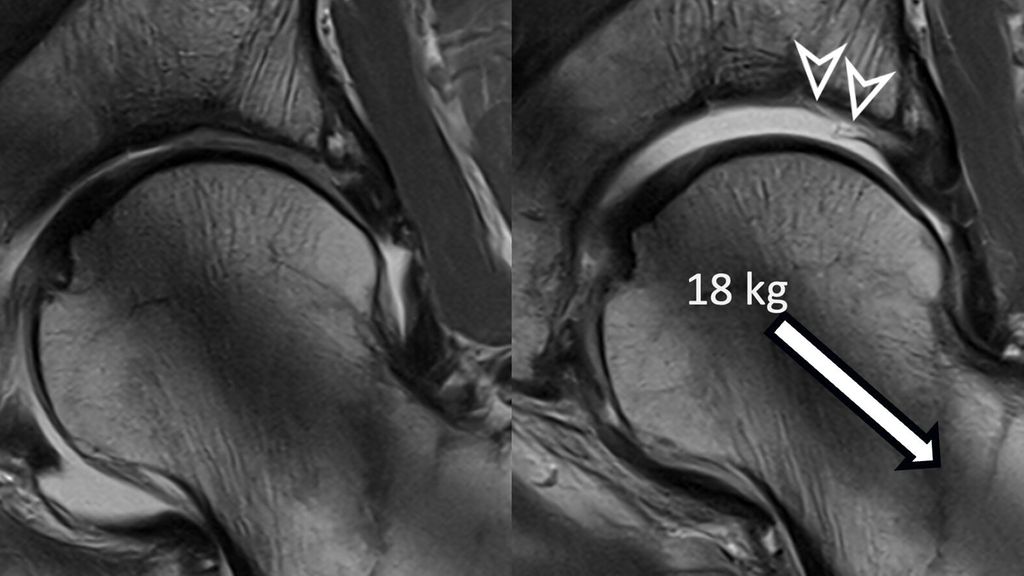

Traction MRI of the hip for improved detection of macroscopic cartilage damage

The hip is a ball-and-socket joint with the labrum dividing it into peripheral and central compartments. In standard MR arthrography, a contrast agent expands the hip capsule and flows into the central joint cavity through the acetabular notch. However, most of the contrast does not spread centrally due to the opposing femoral and acetabular cartilage layers, which typically prevent its accumulation unless there is significant cartilage damage. Therefore, visualizing acetabular cartilage delamination which represents a typical and frequent finding in patients with cam-type FAI is challenging with direct MR arthrography.4

To improve visualization of the central joint cavity during MR arthrography, axial leg traction can be applied, similar to the joint distraction needed during hip arthroscopy (Fig. 1). Traction MR arthrography of the hip has shown high accuracy in detecting chondrolabral lesions, ligamentum teres injuries, and intra-articular loose bodies and has demonstrated its value in predicting failure of FAI surgery.5–8 It is particularly helpful for better visualizing the extent of cartilage damage in older patients with mild radiographic joint degeneration and thus aid in surgical decision making. Traction MR arthrography can also detect unstable labral tears in patients with hip dysplasia and may aid in planning treatment for femoral head necrosis in young patients with early collapse and preserved joint space.4